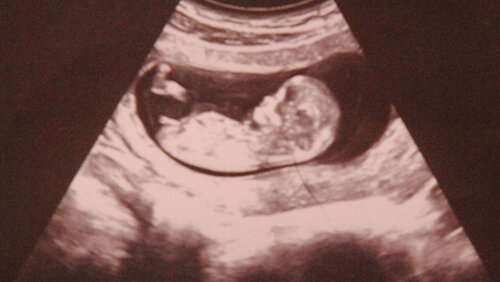

Началась последняя неделя первого триместра, почти все трудности этого периода позади, наступает самое спокойное время. Итак, наступила 13 неделя беременности. Это завершение первой трети гестации, последние дни перед наступлением самого спокойного времени – второго триместра. Женщина беременна уже три месяца и за это время плод из крошечной клетки превратился в маленького человечка. И хотя живот еще не заметен, определенные изменения во внешности и поведении будущей матери окружающие уже заметили...

Что происходит с ребенком на 13 неделе беременности? Это время считается решающим в формировании плаценты. Она заканчивает свое развитие начинает вырабатывать прогестерон и эстроген. Сейчас она берет на себя все основные функции по поддержанию и развитию беременности. Толщина плаценты к этому моменту составляет 16 мм. Пропуская нужные для плода белки, жиры и углеводы, плацента становится барьером на пути различных токсических веществ. Благодаря этому возможно лечение болезней матери, которые требуют применения сильных лекарств...